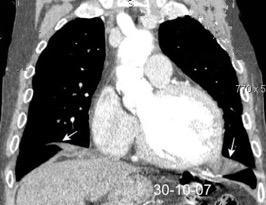

Síndrome de afectación postcardiaca (postcardiac injury)

Post infarto 1-7 % (Dressler)

Trauma cerrado Implantación marcapasos

Cirugía cardiaca. 17-31% (Post.pericardiotomía)

3707 pacientes 29 Derrames (0,78%) > de 25% del hemitórax

Todas menos 2 Izdos.

Angioplastia

By-pass coronario 21-10-03